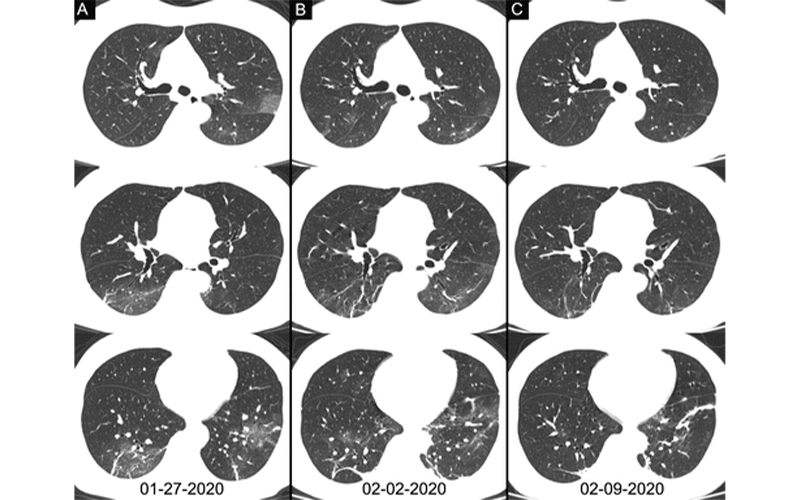

In response to the crisis, Dr. Xia and colleagues quickly launched an investigation of the diagnostic value and consistency of chest CT compared to RT-PCR in detecting COVID-19.

The study included 1,014 patients from Tongji Hospital, the largest hospital in Wuhan. All patients underwent both chest CT and RT-PCR tests between January 6 and February 6, 2020.

With RT-PCR results as the reference standard, the sensitivity, specificity, and accuracy of chest CT in indicating COVID-19 infection were 97% (580 of 601 patients), 25% (105 of 413 patients), and 68% (685 of 1014 patients), respectively. The positive predictive value and negative predictive value were 65% (580 of 888 patients) and 83% (105 of 126 patients), respectively. The results showed that chest CT was more effective than RT-PCR lab testing in detection of COVID-19.

“Our data and analysis suggest that chest CT should be considered for COVID-19 screening, comprehensive evaluation and follow-up, especially in epidemic areas with high pretest probability for disease,” the authors wrote.